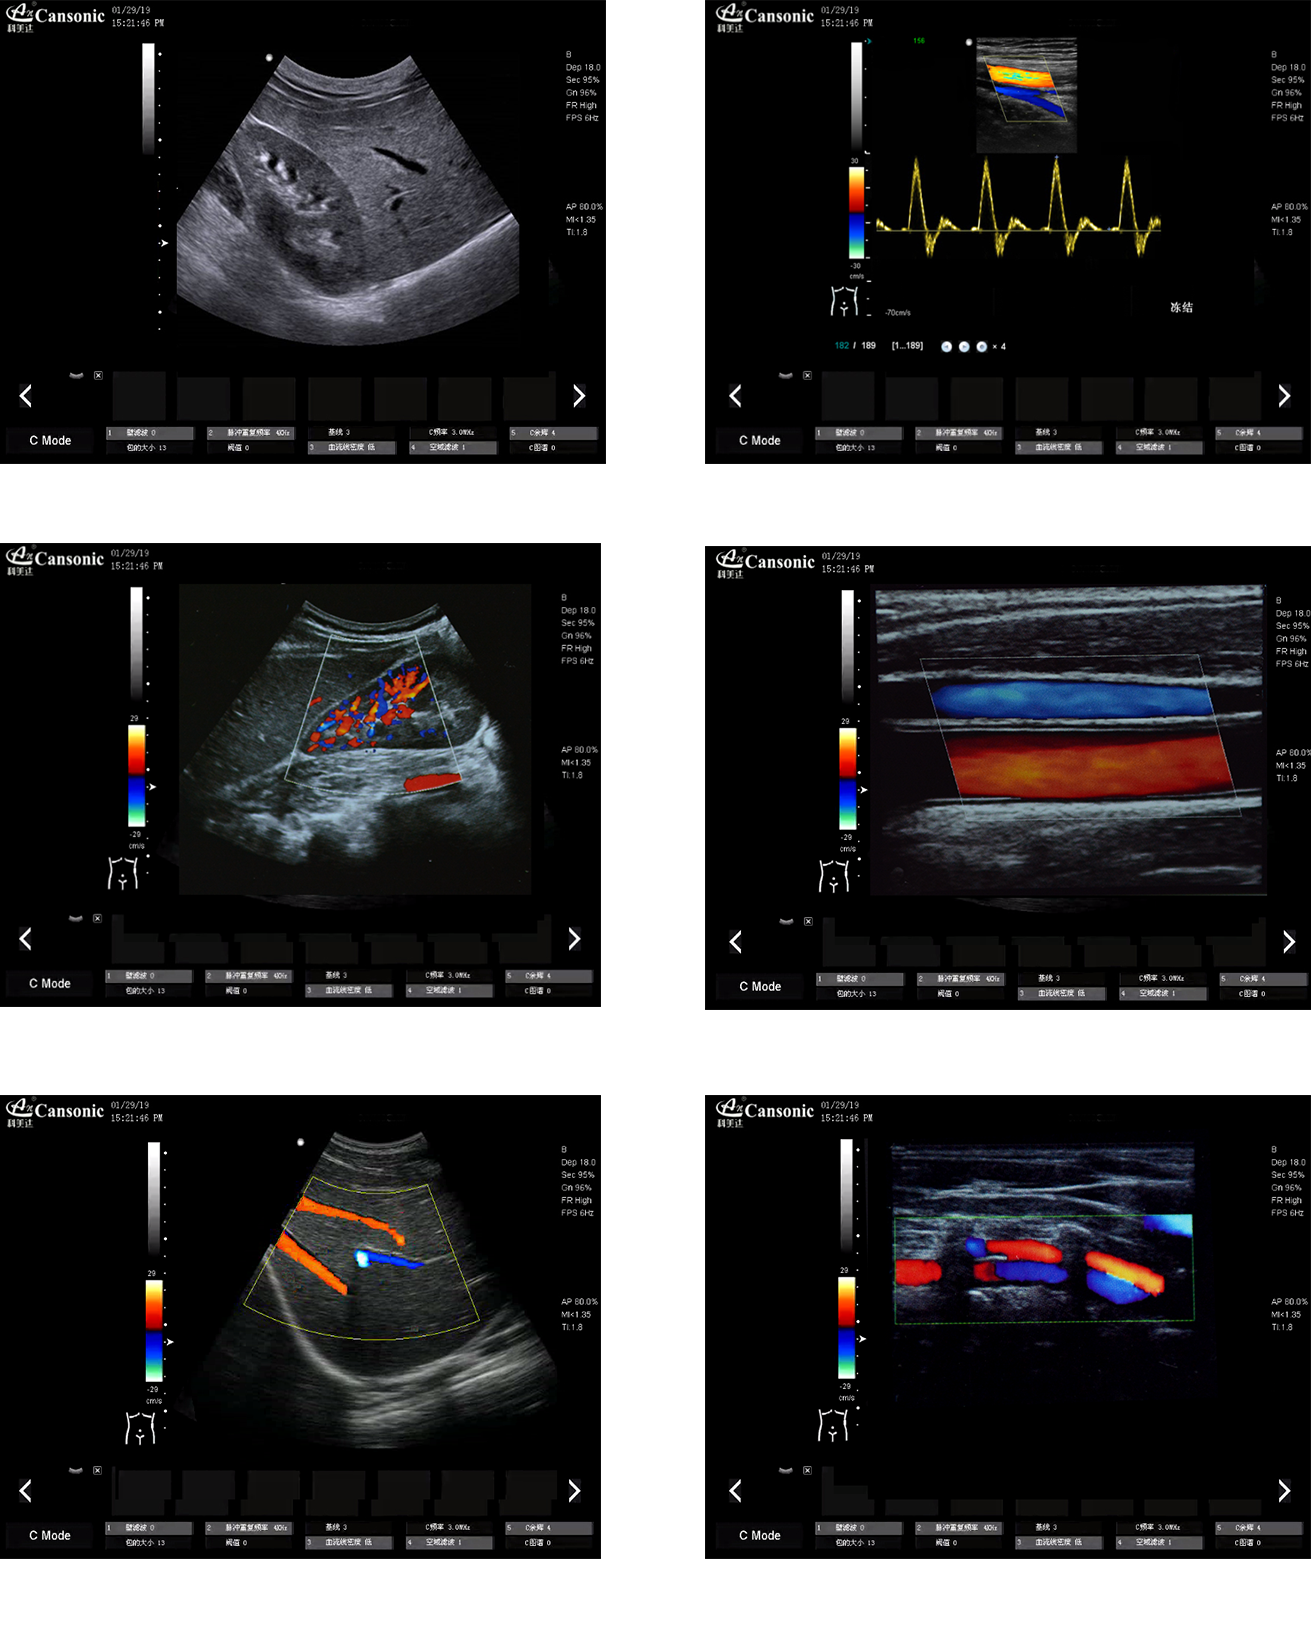

科美達K18圖像實例

1、推車式彩色多普勒全身機,擁有優異的圖像質量和突出的血流顯示效果

2、出色的組織均勻性,減少噪聲干擾,提高圖像顆粒細膩度

3、精細血流識別技術,超寬帶非線性造影成像

4、特異性組織成像結合邊緣增強技術,提供可疑病變更多的邊界信息